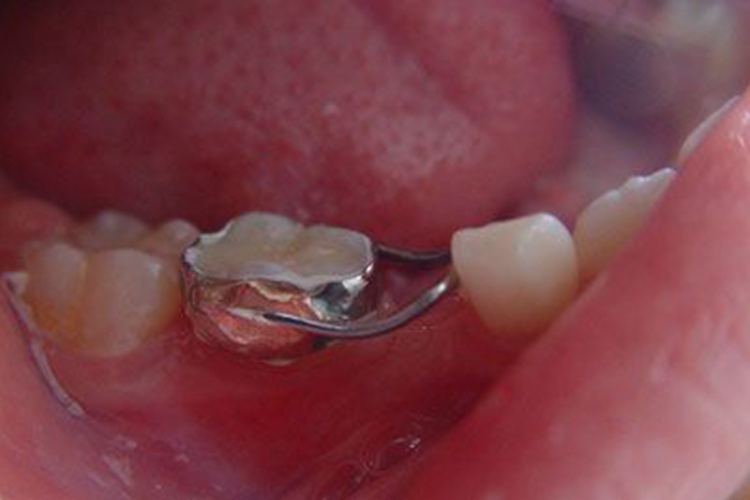

丝圈式间隙保持器

在缺失牙一侧的牙上使用带环或者预成冠、在带环或者预成冠上焊接环状金属丝抵于缺隙另一侧的牙以保持缺失牙间隙的装置。